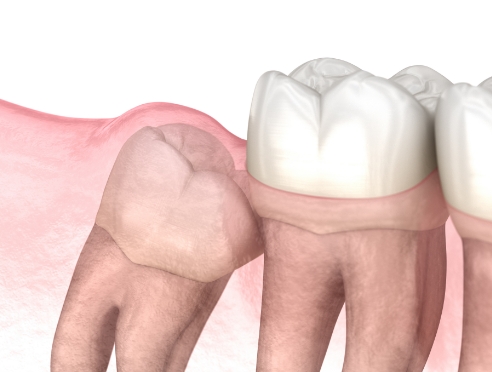

3D CT로 사랑니의 방향, 신경 위치, 주변 치아와의 관계를 세밀하게 확인한 뒤 필요한 경우에 한해 발치를 진행합니다.

불필요한 조직 손상을 최소화하는 방식으로 부담을 줄이며, 환자분이 보다 편안하게 회복하실 수 있도록 돕고 있습니다.